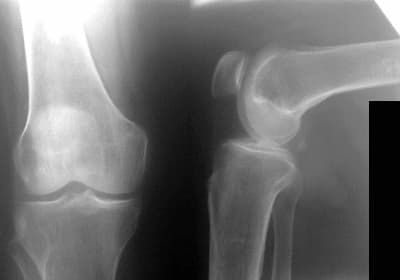

Lalə A: Hər vaxtınız xeyir, mənim nəticələrimə baxın, və deyin zəhmət olmasa, hər şey qorxuludur? Nəyə hazır olmalıyam?

Lalə xanım, sizdə ikinci dərəcəli inkişaf edən artroz var. Müalicədən keçməyiniz tövsiyə olunur və sonra ciddi nəticələrin qarşısını almaq olar. Panikaya düşməyə ehtiyyac yoxdur, hər şey yaxşı olacaq.